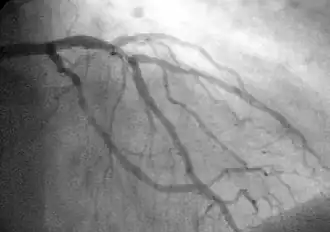

| Coronary arteries providing blood to the heart. The blood vessels originate from the aorta and surround the heart. | |

![]() Showing the coronary arteries that are subject to narrowing - resulting in reduced blood supply to the cardiac muscle. | |